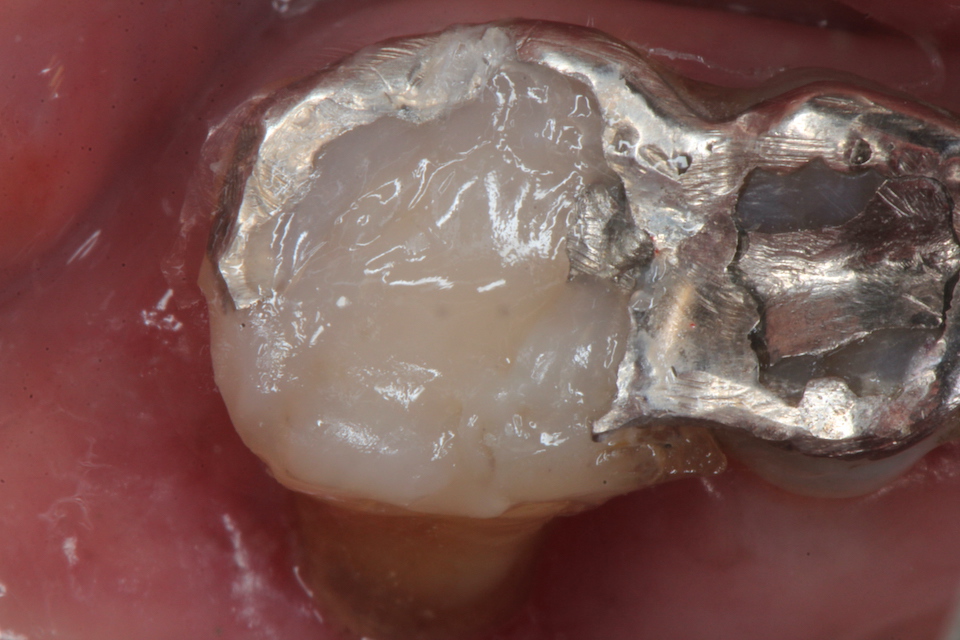

ボスミン液で止血した後は3MIX+α-TCPで根管充填というか直接覆髄というのか、露出している歯髄と根管内を覆うというか注入すればよい。それも緊密充填である必要もない。人間の歯髄というものは非常に丈夫なので炎症があれば全部取る必要があるというのは、これも嘘だ。

α-TCPで充填

CRで漏洩しないようにカバーして終わり。これで痛みや強烈な沁みは消失する。こんな簡単なことで歯髄炎が治るとか信じられないかもしれないが、これが事実だ。冠を被せるまで何度も患者を通わせるなどという患者を苦しめる必要はない